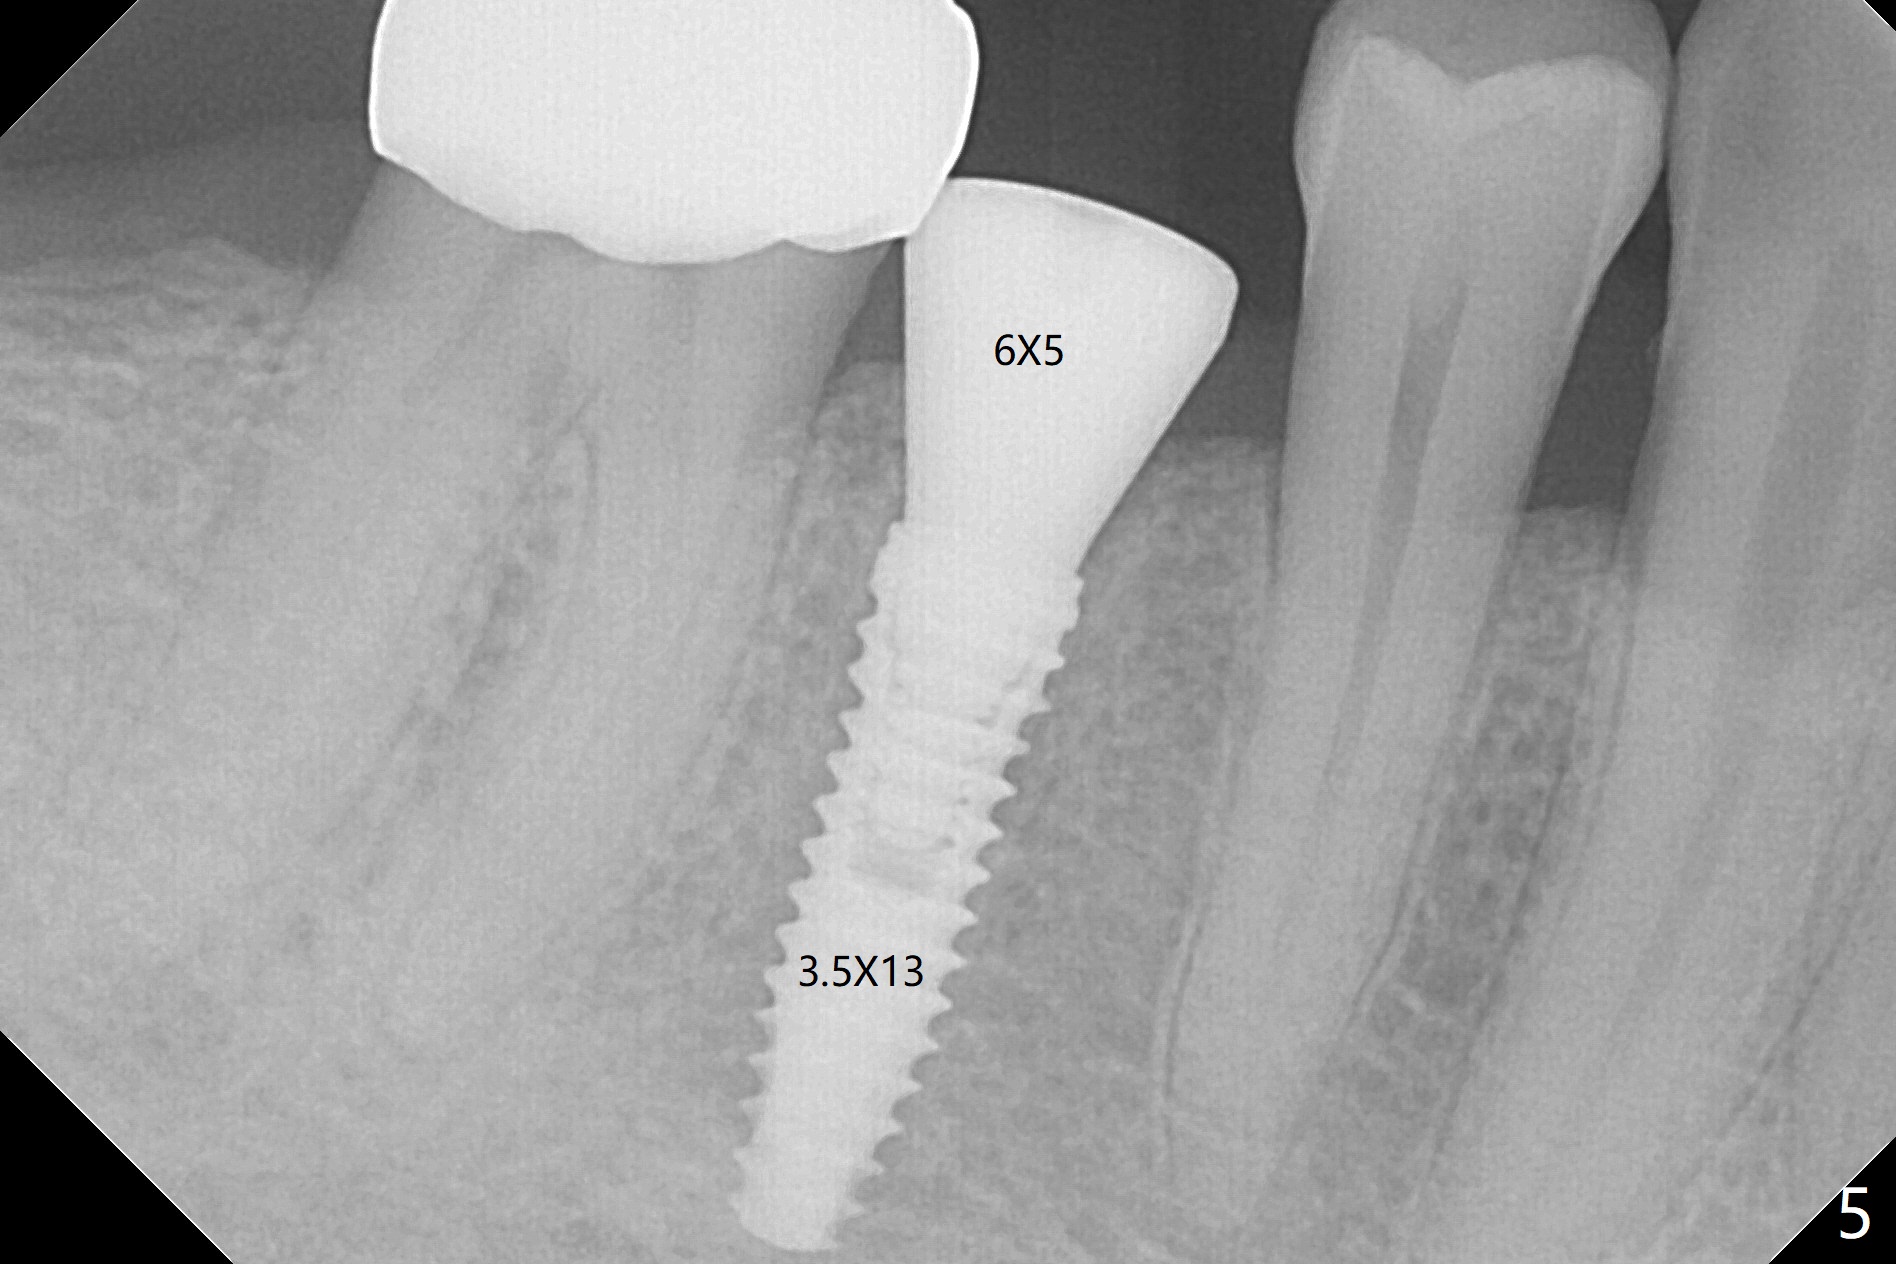

Since the root surface at #29 is distinct (Fig.1), while that at #21 is not (with subgingival caries, Fig.2), closed and open socket shields are done at #29 and 21, respectively (Fig.3,4 S), followed by implant placement with guide (Fig.4-6). With socket shield, there is limited remaining space for bone graft (Fig.4). The shield associated with the closed technique is exposed nearly 2 months postop (Fig.7), while the one associated with the open technique is not (Fig.8). The buccal plate is minimally atrophic with either technique.